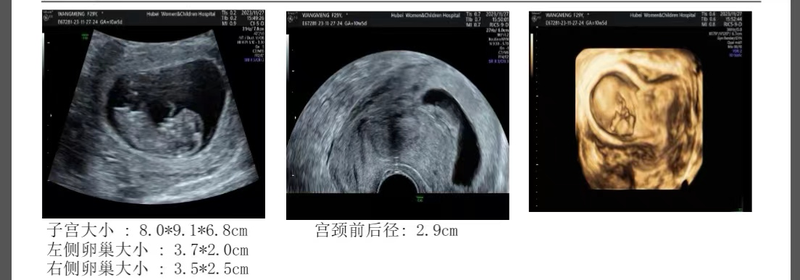

隨著受精卵的著床,標(biāo)志著妊娠的開始,母體的血流動力學(xué)會發(fā)生巨大的變化,妊娠期胎兒的生長發(fā)育依賴于母體的血液供應(yīng),妊娠早期母胎之間形成子宮-胎盤循環(huán),保證胎兒的正常發(fā)育,所以子宮動脈的血液循環(huán)則顯得至關(guān)重要。一子宮動脈與不良妊娠結(jié)局的病理生理子宮血供來源于子宮動脈及其分支,包括供應(yīng)子宮肌層的弓形動脈及子宮內(nèi)膜的螺旋動脈;子宮動脈為女性子宮提供養(yǎng)分,在孕期子宮動脈血流循環(huán)的正常運行對于妊娠則至關(guān)重要。成功的妊娠依賴于在母體與胎兒之間適當(dāng)轉(zhuǎn)運氧氣、營養(yǎng)和廢物,對這一點至關(guān)重要的是在妊娠早期子宮-胎盤循環(huán)空間(UPCS)的滋養(yǎng)層介導(dǎo)的發(fā)育過程,UPCS是氧氣和營養(yǎng)交換發(fā)生的位置,在UPCS形成過程中,移出血管的滋養(yǎng)細(xì)胞侵入螺旋狀動脈壁,將它們從小口徑、高阻的血管轉(zhuǎn)變成寬口徑、低阻力的血管,這些血管將血液輸送到低氣壓的絨毛間隙。其形成包括滋養(yǎng)層入侵和螺旋動脈重塑,分為兩個階段,第一階段發(fā)生在8-10周,第二階段發(fā)生在14-16周,UPCS的發(fā)育不足進(jìn)而會導(dǎo)致了胎盤的阻力增加,從而導(dǎo)致子宮動脈阻力的增加。在正常妊娠中,子宮動脈的阻力隨著妊娠的推進(jìn)而減小,獲得低阻力循環(huán)的失敗與隨后的妊娠不良結(jié)局的風(fēng)險相關(guān)。受損的胎盤與螺旋動脈的滋養(yǎng)層入侵失敗或不足有關(guān),從而增加了子宮動脈血流的阻力。子宮-胎盤循環(huán)處于高阻力狀態(tài)將導(dǎo)致廣泛的內(nèi)皮細(xì)胞損傷,損害血管的完整性,并在小動脈中形成動脈粥樣硬化的過程,最終導(dǎo)致血管閉塞、局部缺血壞死,進(jìn)而導(dǎo)致胚胎停止發(fā)育、子癇前期、胎兒生長受限等妊娠不良結(jié)局的發(fā)生。二子宮動脈與不良妊娠結(jié)局病理狀態(tài)下,滋養(yǎng)細(xì)胞對胎盤螺旋動脈的侵蝕受到抑制,子宮肌層螺旋動脈保持原狀不擴(kuò)張或輕度擴(kuò)張,母體血流通過血管所受阻力較正常妊娠大,單位時間內(nèi)注入絨毛間隙的母體血流少,影響胚胎的生長和發(fā)育,RI和S/D處于高水平狀態(tài),易導(dǎo)致胚胎停止發(fā)育、妊娠期高血壓疾病,胎兒生長受限,羊水過少等并發(fā)癥。病歷分享郭女士,33歲,胚胎停止發(fā)育2次;第一次:2021年5月孕7周,有卵黃囊胎芽胎心,胚停后行藥流+清宮術(shù);第二次:2023年4月孕6+周,有卵黃囊、無胎芽胎心,自然流產(chǎn)。此次懷孕末次月經(jīng)2023年10月25日,11月23日查血HCG94.2mIU/ml提示懷孕,遂來我院要求妊娠監(jiān)督,防止流產(chǎn)再次發(fā)生;11月29日孕35天彩超示雙側(cè)子宮動脈19.15,給予中藥丹川顆??诜谄溥m量活動;12月5日孕41天復(fù)查彩超示雙側(cè)子宮動脈20.44,停用丹川顆粒改為丹參川芎嗪注射液100ml靜脈輸液;12月8日孕44天復(fù)查彩超示雙側(cè)子宮動脈21.25,繼續(xù)給予丹參川芎嗪注射液100ml靜脈輸液,同時加用魯南欣康20mg陰道上藥3天;12月11日孕47天復(fù)查彩超示雙側(cè)子宮動脈13.37較前明顯下降,停用丹參川芎嗪注射液;此后多次復(fù)查彩超雙側(cè)子宮動脈均在正常范圍內(nèi)波動;同時監(jiān)測血HCG翻倍佳,峰值達(dá)189437mIU/ml;具體情況可看上圖三總結(jié)妊娠期胎兒的生長發(fā)育依賴于母體的血液供應(yīng),母體的血液供應(yīng)決定了胎盤的供血供氧,所以胎兒的正常發(fā)育完全依靠子宮動脈的血液循環(huán)。孕前或孕早期監(jiān)測子宮動脈是很重要的,若發(fā)現(xiàn)子宮動脈阻力高,及時給予藥物對癥治療,可提高胚胎著床率,改善不良妊娠結(jié)局的發(fā)生率。參考文獻(xiàn):【1】子宮動脈預(yù)測妊娠不良結(jié)局及并發(fā)癥的進(jìn)展盧磊劉繼紅代樹花【2】早孕前、后子宮動脈血流與妊娠結(jié)局相關(guān)性研究李紳王美耿順玲付錦華